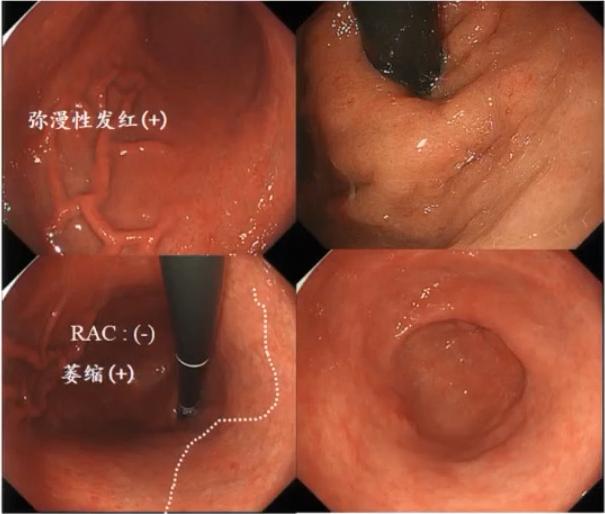

感染是一个炎症(红、肿、痛)过程,Hp感染后的胃黏膜在内镜下的直观表现为——黏膜肿胀、黏液分泌增多,胃体、胃底部出现弥漫性红斑。

Hp感染后的胃黏膜表现。

1.未发生胃黏膜萎缩的患者

未发生胃黏膜萎缩的患者Hp根除前后黏膜变化。

根除前:黏膜点状发红,黏膜皱襞增粗;

根除后:发红现象消失,黏膜更清晰。

2.发生胃黏膜萎缩的患者

胃黏膜萎缩患者在Hp根除后,炎症的修复相对不明显。

胃黏膜萎缩患者Hp根除前后内镜下表现。

根除后红斑、炎症消退,但依然可见明显萎缩,伴有部分红斑残留。

Kyto胃炎分型的内镜表现有助于诊断Hp感染状态,具体为:

➤现症Hp感染:弥漫红斑、黏膜肿胀、黏膜黏液、粗大皱襞

➤既往Hp感染(根除后)表现:地图样红斑